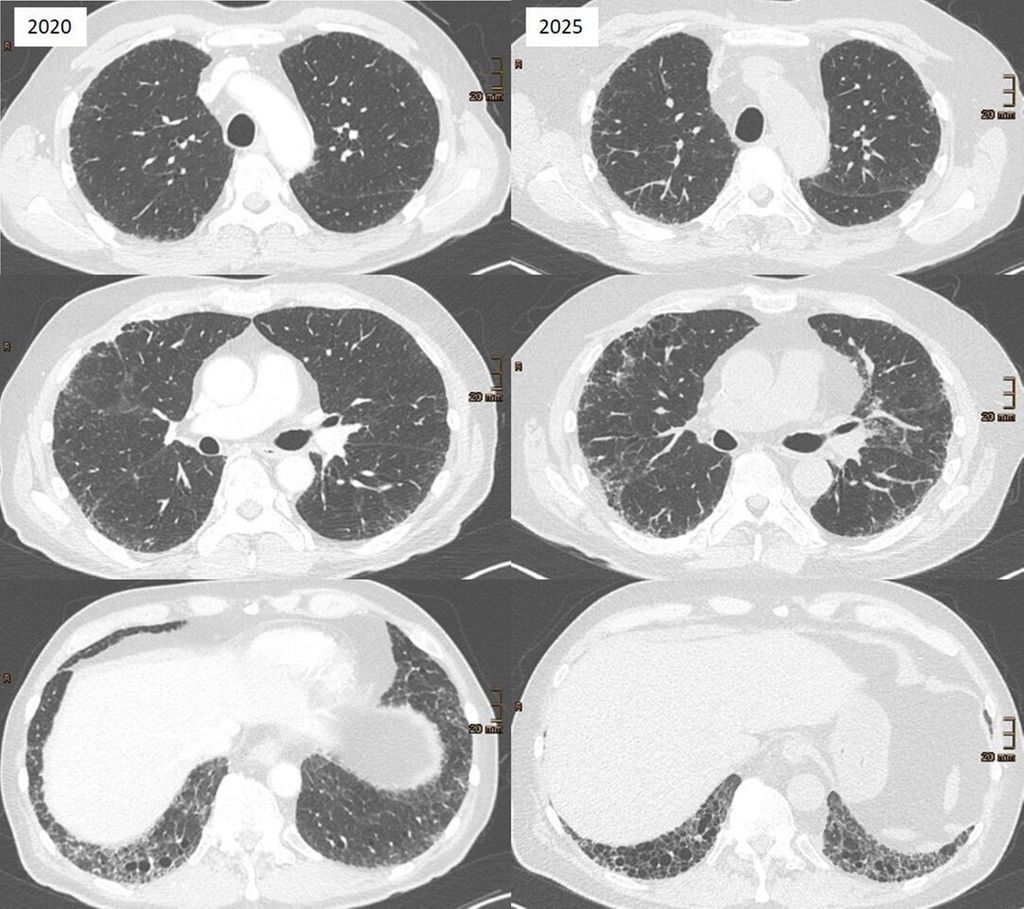

Interstitielle Lungenanomalien sind radiologische Veränderungen, die typischerweise als Zufallsbefund bei CT-Untersuchungen entdeckt werden. Nach der Fleischner-Definition von 2020 handelt es sich um bilaterale, nichtgravitationsabhängige Lungenveränderungen wie Milchglastrübungen, Retikulationen, Traktionsbronchiektasen oder Honeycombing (Honigwabenmuster), die mindestens 5% eines Lungenareals betreffen.19 Die neue Definition der American Thoracic Society (ATS) von 2025 erweitert diese Kriterien, indem sie auch Hochrisikopatient:innen ohne klassischen Zufallsbefund einschließt.2 ILA gelten heute als prämorbides Stadium einer ILD (Abb.1). In einer großen retrospektiven Studie bei 1699 Teilnehmer:innen eines Lungenkrebs-Screenings entwickelten 25% der Personen mit ILA im Verlauf eine manifeste ILD; die mediane Zeit bis zur Diagnose betrug 4,5 Jahre. Zudem war ILA ein unabhängiger Mortalitätsprädiktor.2

Abb. 1: Beispiel eines progredienten Verlaufs von interstitiellerLungenanomalie (ILA) zu interstitieller Lungenerkrankung (ILD)

Die klinischen Risikofaktoren für eine Progression von ILA zu ILD umfassen Nikotinkonsum und inhalative Expositionen, vorausgegangene onkologische Therapien sowie eine abnorme oder grenzwertige Lungenfunktion (z.B. eingeschränkte FVC, DLCO oder TLC). Zu den radiologischen Risikofaktoren zählen ILA subpleuraler oder basaler Dominanz, das Vorliegen von Honeycombing und Traktionsbronchiektasen sowie ein ausgedehnter Befall einzelner Zonen oder ganzer Lungenabschnitte.